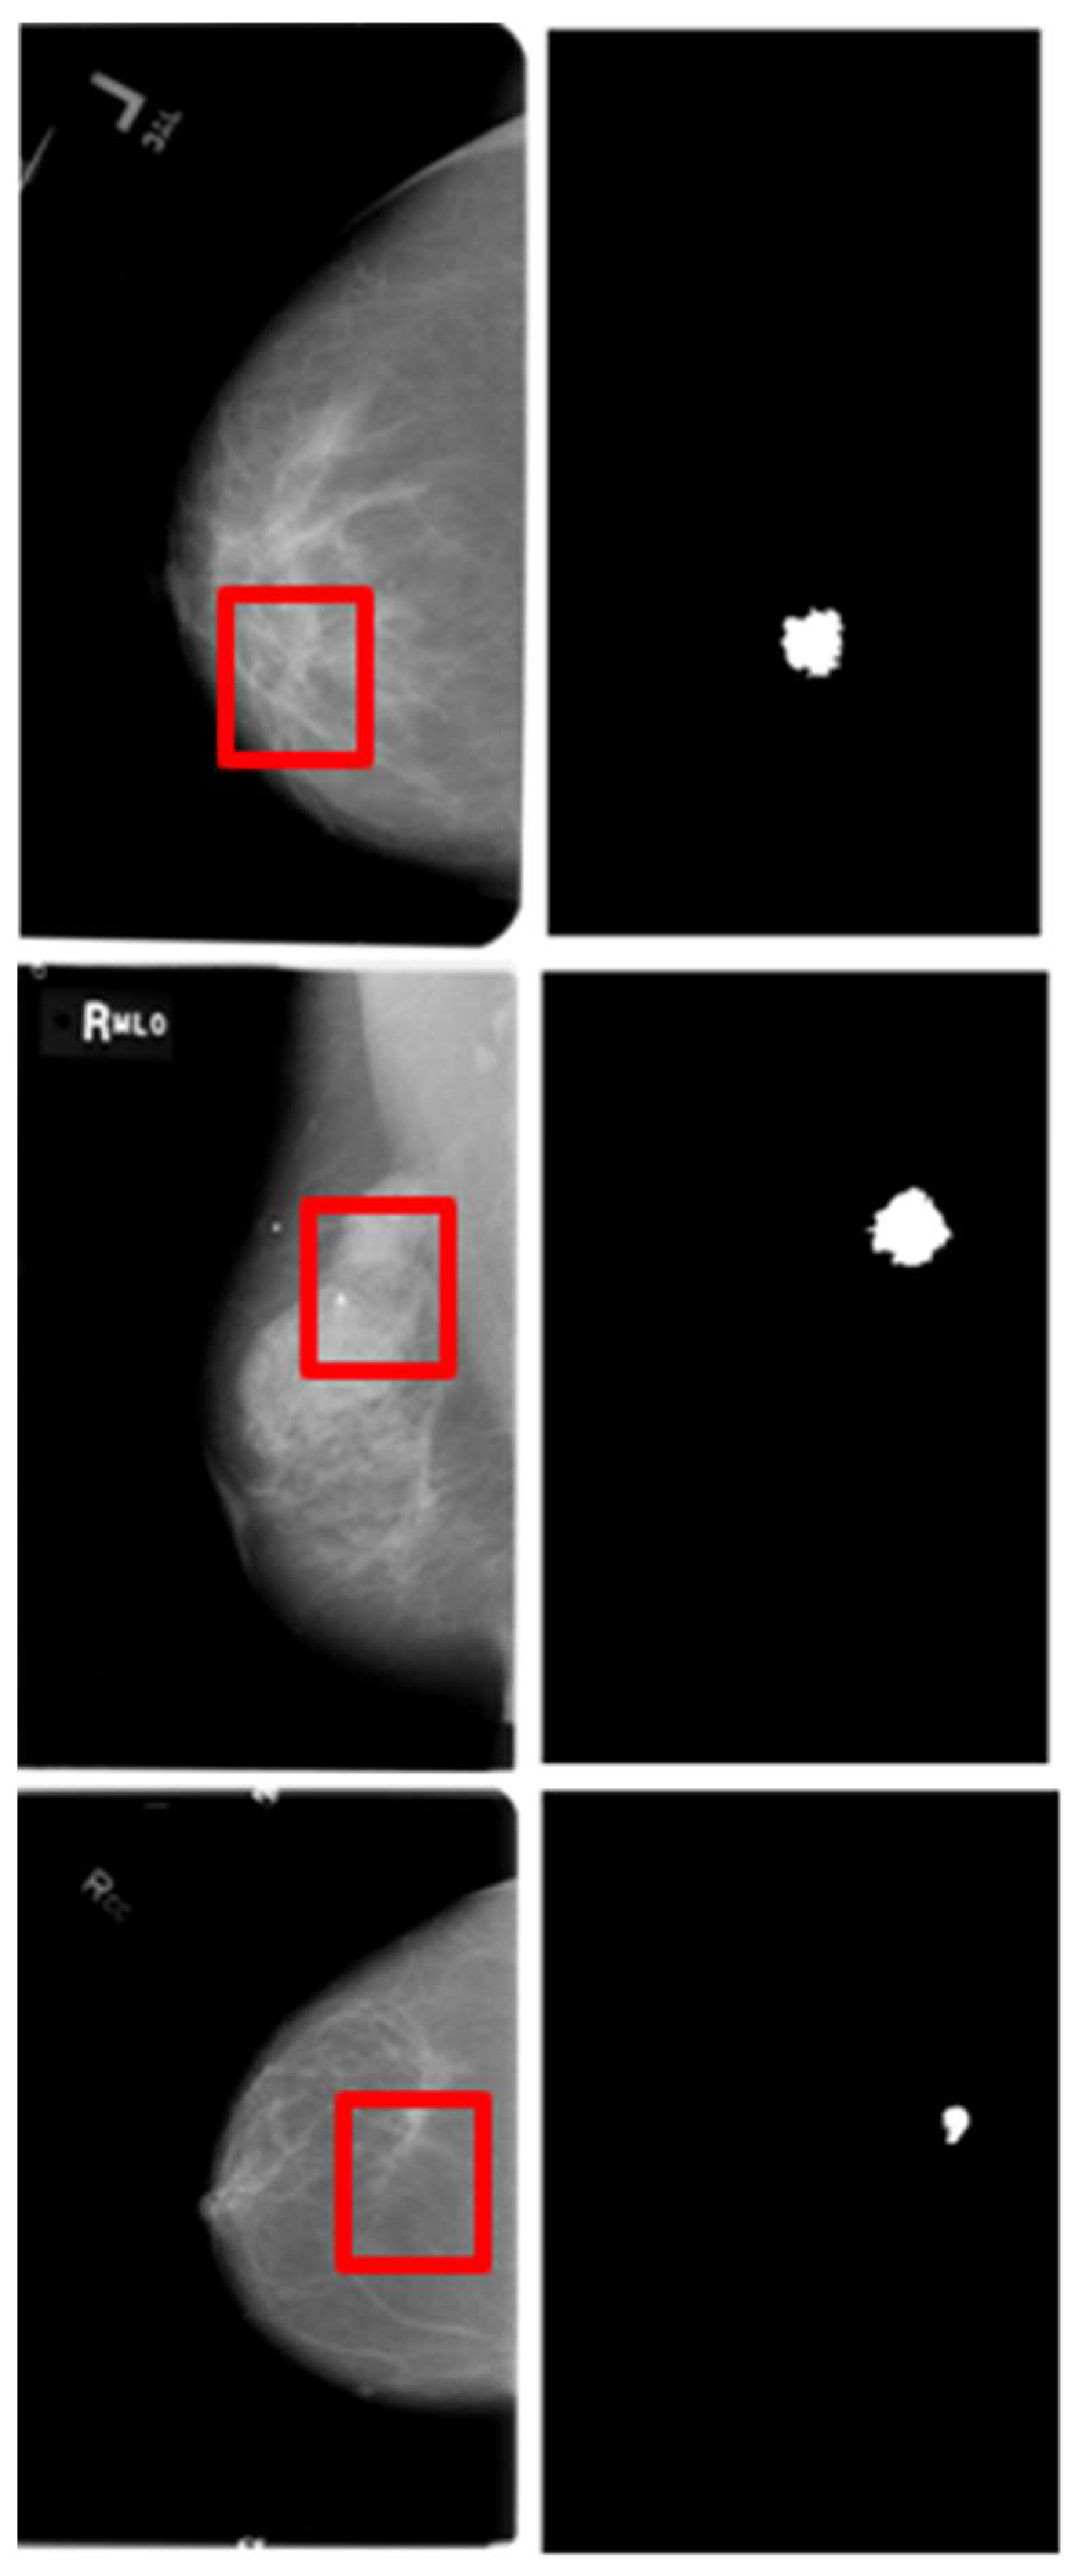

The Curated Breast Imaging Subset of the DDSM (CBIS-DDSM) is a dataset containing a substantial number of mammography images, which can be accessed via The Cancer Imaging Archive (TCIA). These images are utilized for various tasks, including lesion detection, segmentation, and classification [21,22,23].

The challenge of this dataset lies in its original image size, which is significantly larger than the masses that constitute the regions of interest, characterized by subtle texture appearances in segmentation tasks. The image resolutions range from 753x1028 to 6871x5431, while the bounding box dimensions enclosing regions of interest vary from 126x124 to 962x936. Image examples are illustrated in Figure 6.

CBIS-DDSM provides 1301 training and 377 testing images of masses, along with their corresponding ground truth masks. Furthermore, these images are meticulously annotated and include views captured in both craniocaudal and mediolateral oblique orientations.

Figure 6. Images from CBIS-DDSM dataset.